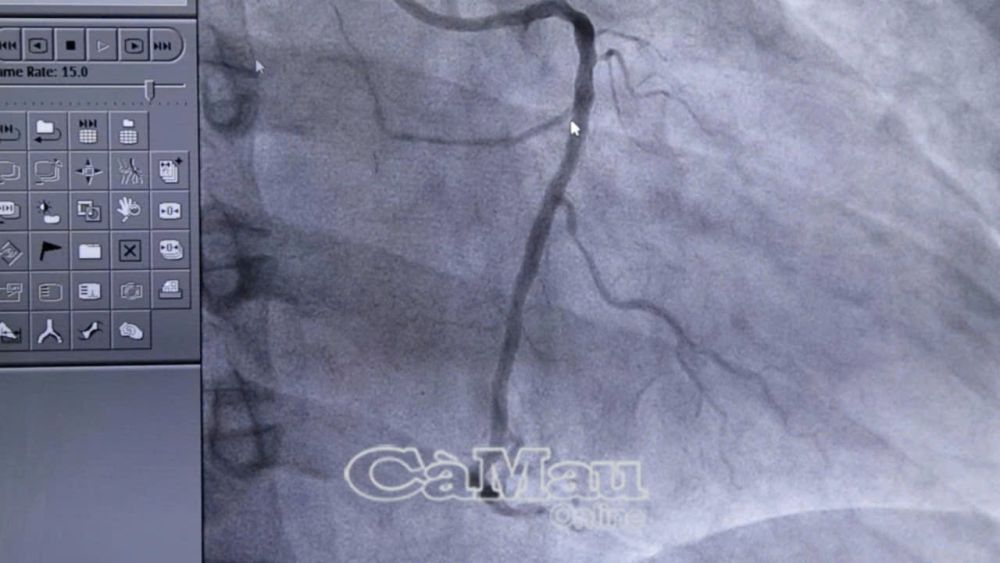

Hình ảnh từ hệ thống chụp mạch máu xoá nền DSA cho thấy nhánh động mạch vành phải bị tắc nghẽn hoàn toàn trước khi can thiệp.

Động mạch vành phải được tái thông thành công sau can thiệp đặt stent, giúp khôi phục dòng máu nuôi tim.